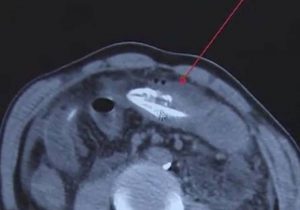

"Sospechábamos que había un objeto extraño en su cavidad abdominal por una tomografía computarizada que se le realizó al paciente, pero no podíamos saber de dónde venía", comentó uno de los especialista que atendió a la víctima.